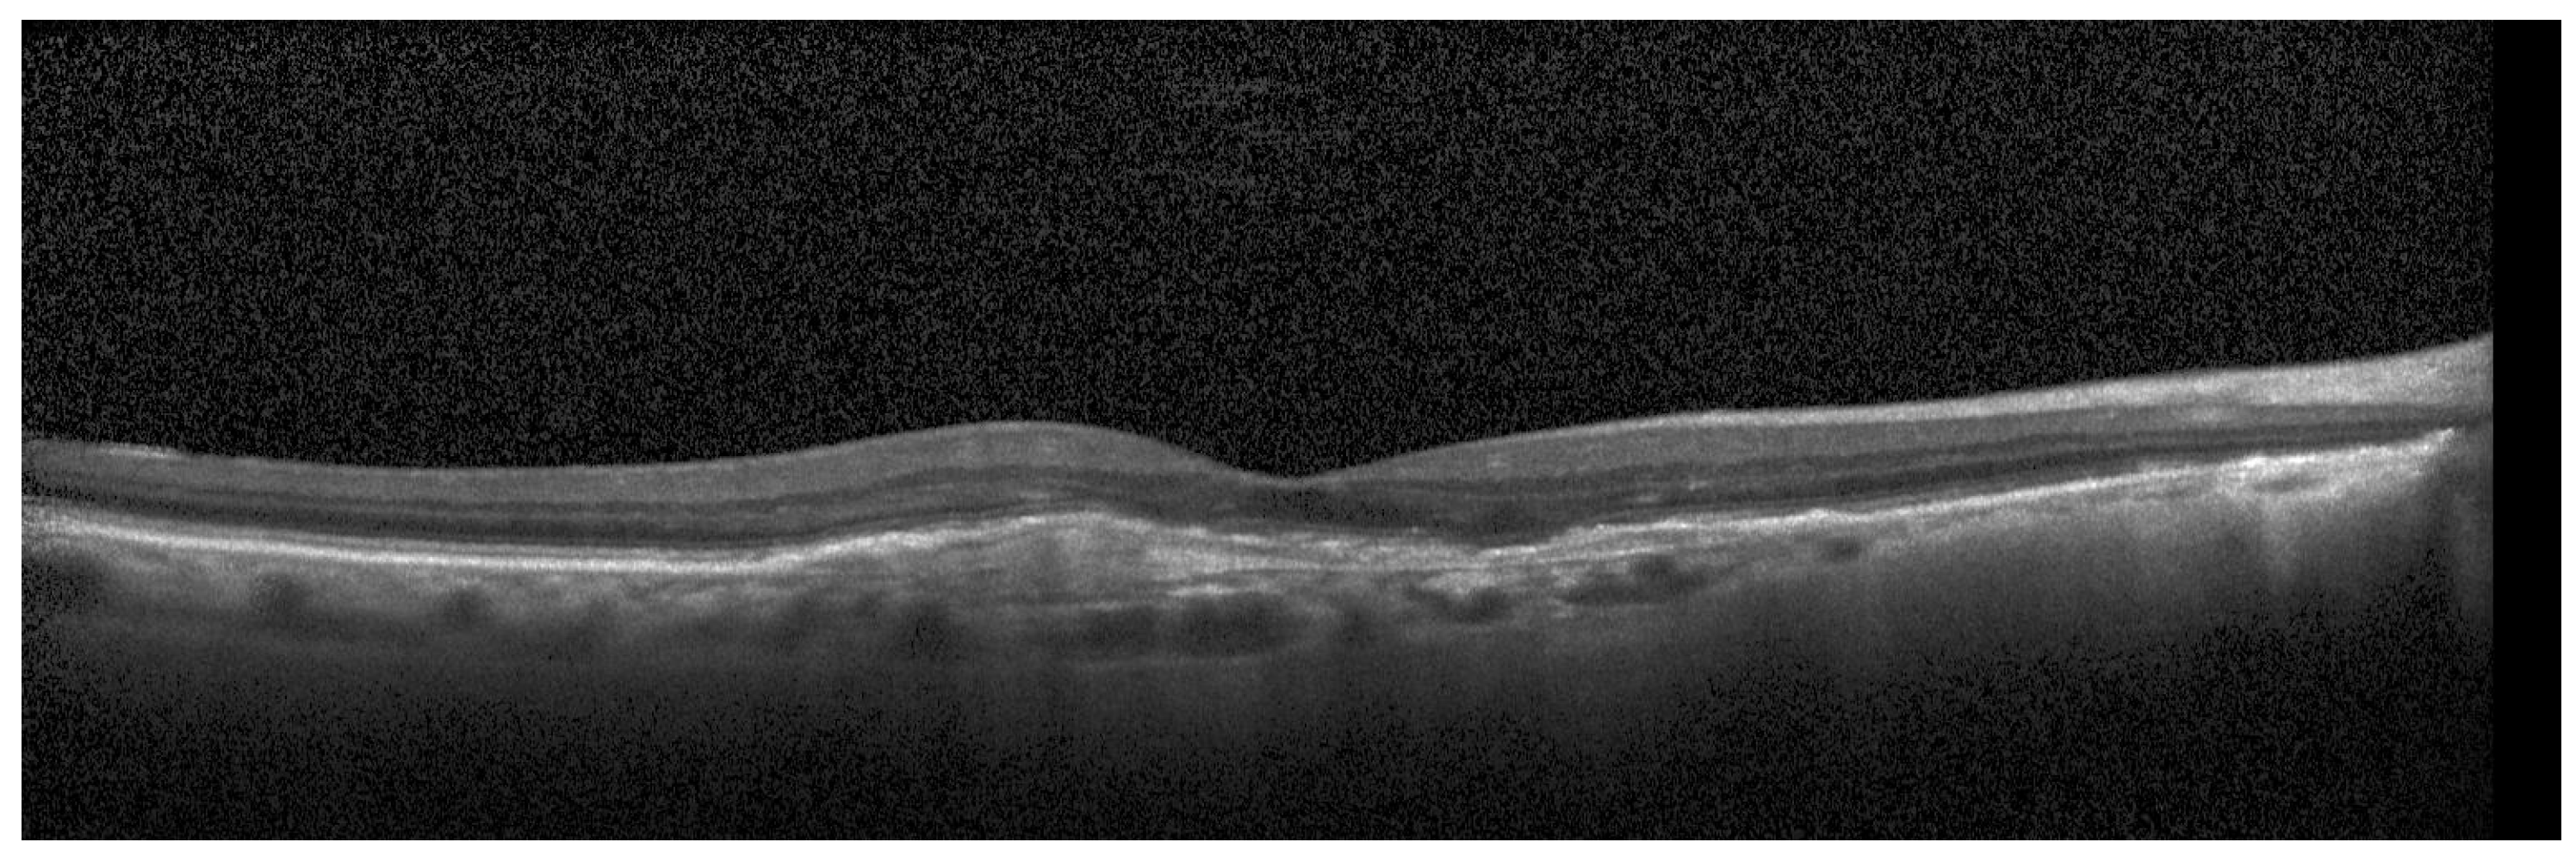

For the testing purpose and the presentation of the image manipulation detection method in the following section, the Optical Coherence Tomography (OCT) images, having the resolution of 1536 × 496 pixels, were used [33]. The OCT is a non-invasive imaging examination that uses light waves to take cross-section pictures of the human retina. One sample image of this type is shown in Figure 3. The tests show that the blocks: 37–39, 45–47, and 53–55, marked in Figure 4, should be usually selected for the process of inserting secret information. This conclusion is based on the analysis of spectra of diverse images with varying content and characteristics. For the selection of the best channel for watermark embedding, the mean of all absolute values from each block is calculated. The channel with the lowest mean is chosen as the first candidate for the subsequent data embedding operation. To increase the capacity of the watermark, other blocks can be selected afterward, considering their mean values sorted in ascending order.

Figure 3.

Sample OCT image.